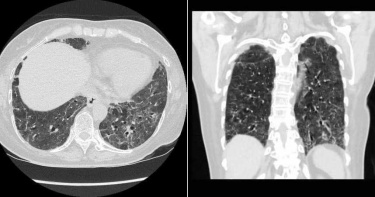

新冠肺炎爆發至今,全球持續對抗疫情,而有不少確診案例都出現「肺部纖維化」的症狀,病患可能會因呼吸衰竭導致死亡。台北市立聯合陽明醫院胸腔醫師蘇一峰表示,嚴重肺纖維化將會縮短10-20年的剩餘壽命,人生從此變黑白。蘇一峰透露,目前手上有3個新冠肺炎痊癒者產生肺纖維化,其中一名患者甚至沒辦法脫離氧氣;臨床上越來越多新冠肺炎的倖存者產生肺纖維化情形,而過去大陸研究也指出,中度新冠肺炎患者有8成會在之後出現肺纖維化,重度患者則全部產生肺纖維化。蘇一峰提及,越早使用抗纖維化藥物能幫助減少日後發生肺纖維化,但目前健保不給付抗肺纖維化藥物,窮苦弱勢族群吃不起藥物。他補充,一周藥費5000至一萬,至少吃3個月才能看出效果,約5到10萬元一個療程。而最近,他為了一名買不起肺纖維化治療藥物的肺纖維化患者,拚命打電話拜託幾家廠商幫忙,終於得到一家廠商的回覆,提供一盒免費的藥物給窮苦的肺纖維化患者使用,但總不能一直凹藥廠免費提供治療。他不禁大嘆,「不知該如何幫助這群窮苦患者。」蘇一峰強調,產生嚴重肺纖維化將會縮短10-20年的剩餘壽命,也可能讓人生提早依賴氧氣與呼吸器,人生從此變成黑白的,因此希望大家還是要好好保護自己,做好防疫工作。